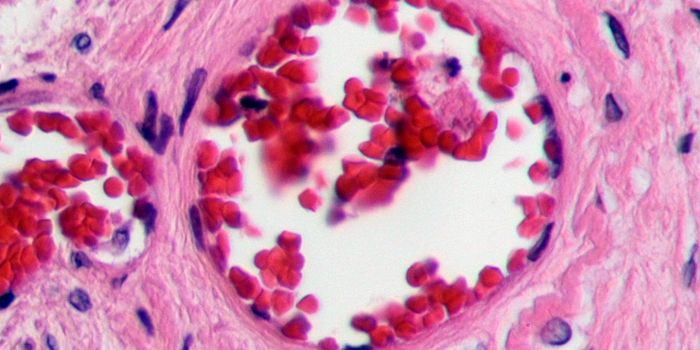

SEP 17, 2020Clinical & Molecular DXBlood clotting, also known as coagulation, is a critical biological mechanism to prevent excessive blood loss in the eve ...